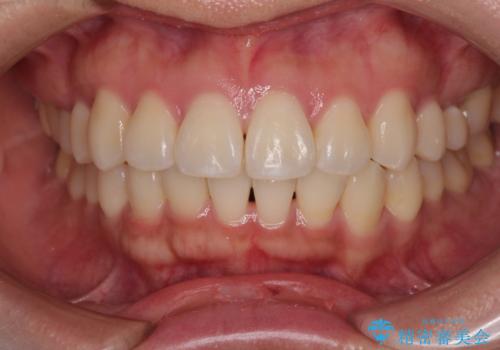

デコボコと正中のずれを改善した矯正治療

「歯並びと正中が整って、自信をもって笑えるようになった」

と大変ご満足のお言葉をいただきました。